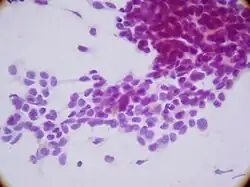

In histopathology, a small-blue-round-cell tumour (abbreviated SBRCT), also known as a small-round-blue-cell tumor (SRBCT) or a small-round-cell tumour (SRCT), is any one of a group of malignant neoplasms that have a characteristic appearance under the microscope, i.e. consisting of small round cells that stain blue on routine H&E stained sections.

These tumors are seen more often in children than in adults. They typically represent undifferentiated cells. The predominance of blue staining is because the cells consist predominantly of nucleus, thus they have scant cytoplasm.[1][2]